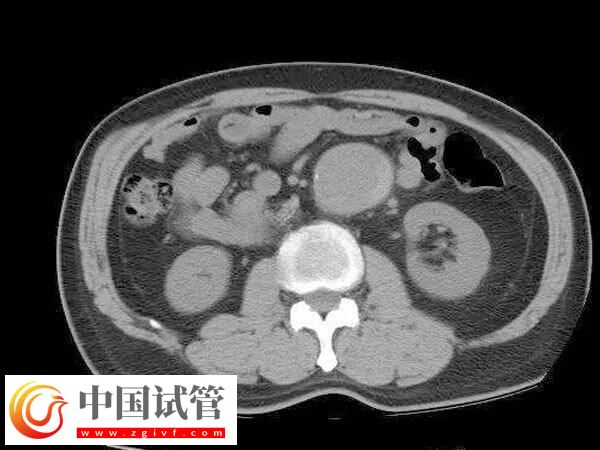

4、利用腹腔鏡探查盆腔以了解子宮大小形態和位置與周圍臟器關系。